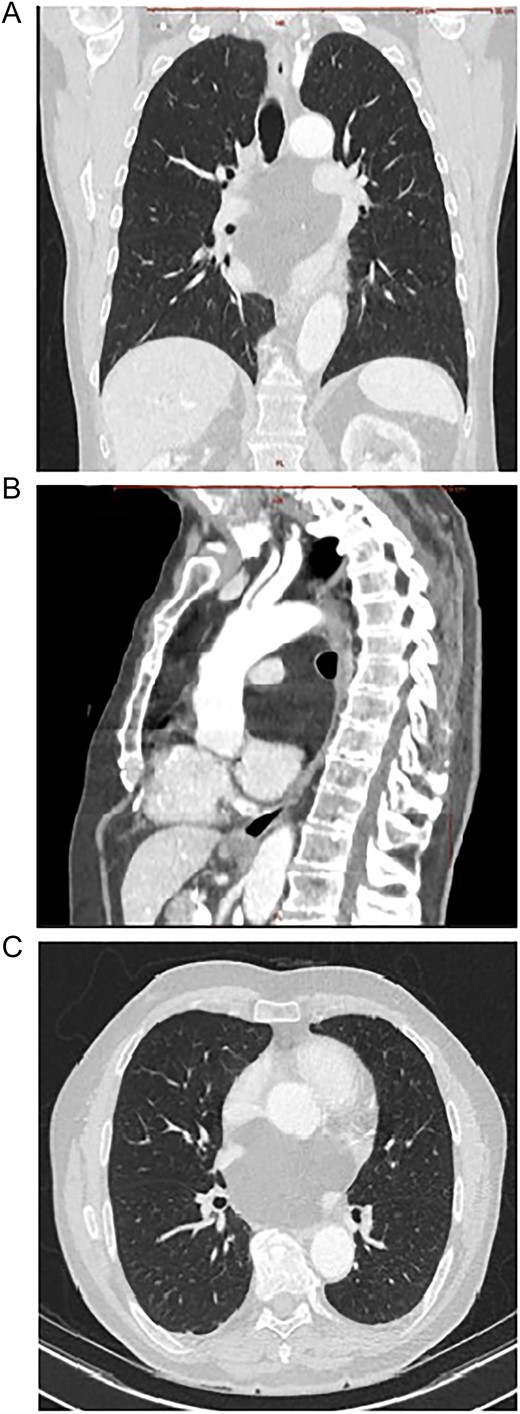

A 75-year-old Caucasian man presented with worsened retrosternal pressure, decline in performance and syncope episodes. The patient was investigated 2-years earlier for performance intolerance, revealing a 9 × 8.5 cm mediastinal retrocardiac lesion in a computed tomography (CT)-scan, initially classified as oligosymptomatic. The progredient symptomatology prompted a new CT-scan showing a slight increase in size of the lesion to 8 × 10 cm, compression of the left atrium and pulmonary veins bilaterally (Fig. 1A–C). An echocardiography performed at rest demonstrated a regular cardiac output with no obstruction of flow in the pulmonary veins or arteries. A pre-operative diagnosis of a benign lipoma was suspected. Interdisciplinary concerns about a potentially abrupt and fatal insufficiency during increased exercise led to the referral to surgery.

Contrast enhanced CT scan of mediastinum demonstrating the well-defined focal fat-attenuated homogenous lesion. (A) Coronal view, (B) sagittal view, (C)axial view.